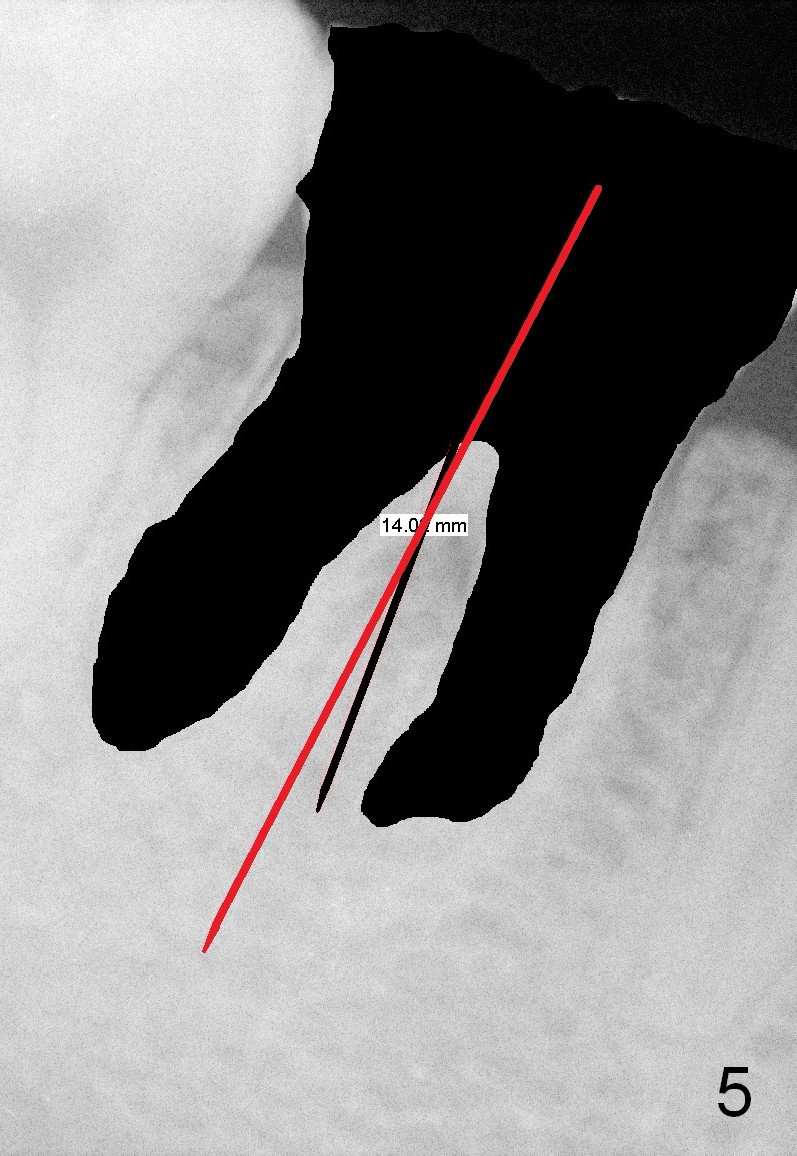

First of all, use a sharp small pilot drill (1.2, 1.5 or 2.0 mm) 3 mm shy of the extended length.  For this case, the initial depth will be 14 mm from the gingival margin (Fig.3: red long arrow).  If the drill is straight and in the middle of the septum (1st intraop PA), keep drilling for the next 3 mm.  If the trajectory is off (Fig.4), withdraw the drill (Fig.5 black long arrow), find a new starting point, change the trajectory and finish osteotomy depth (red long arrow) if the new trajectory is deemed correct.  Take more X-ray if necessary.